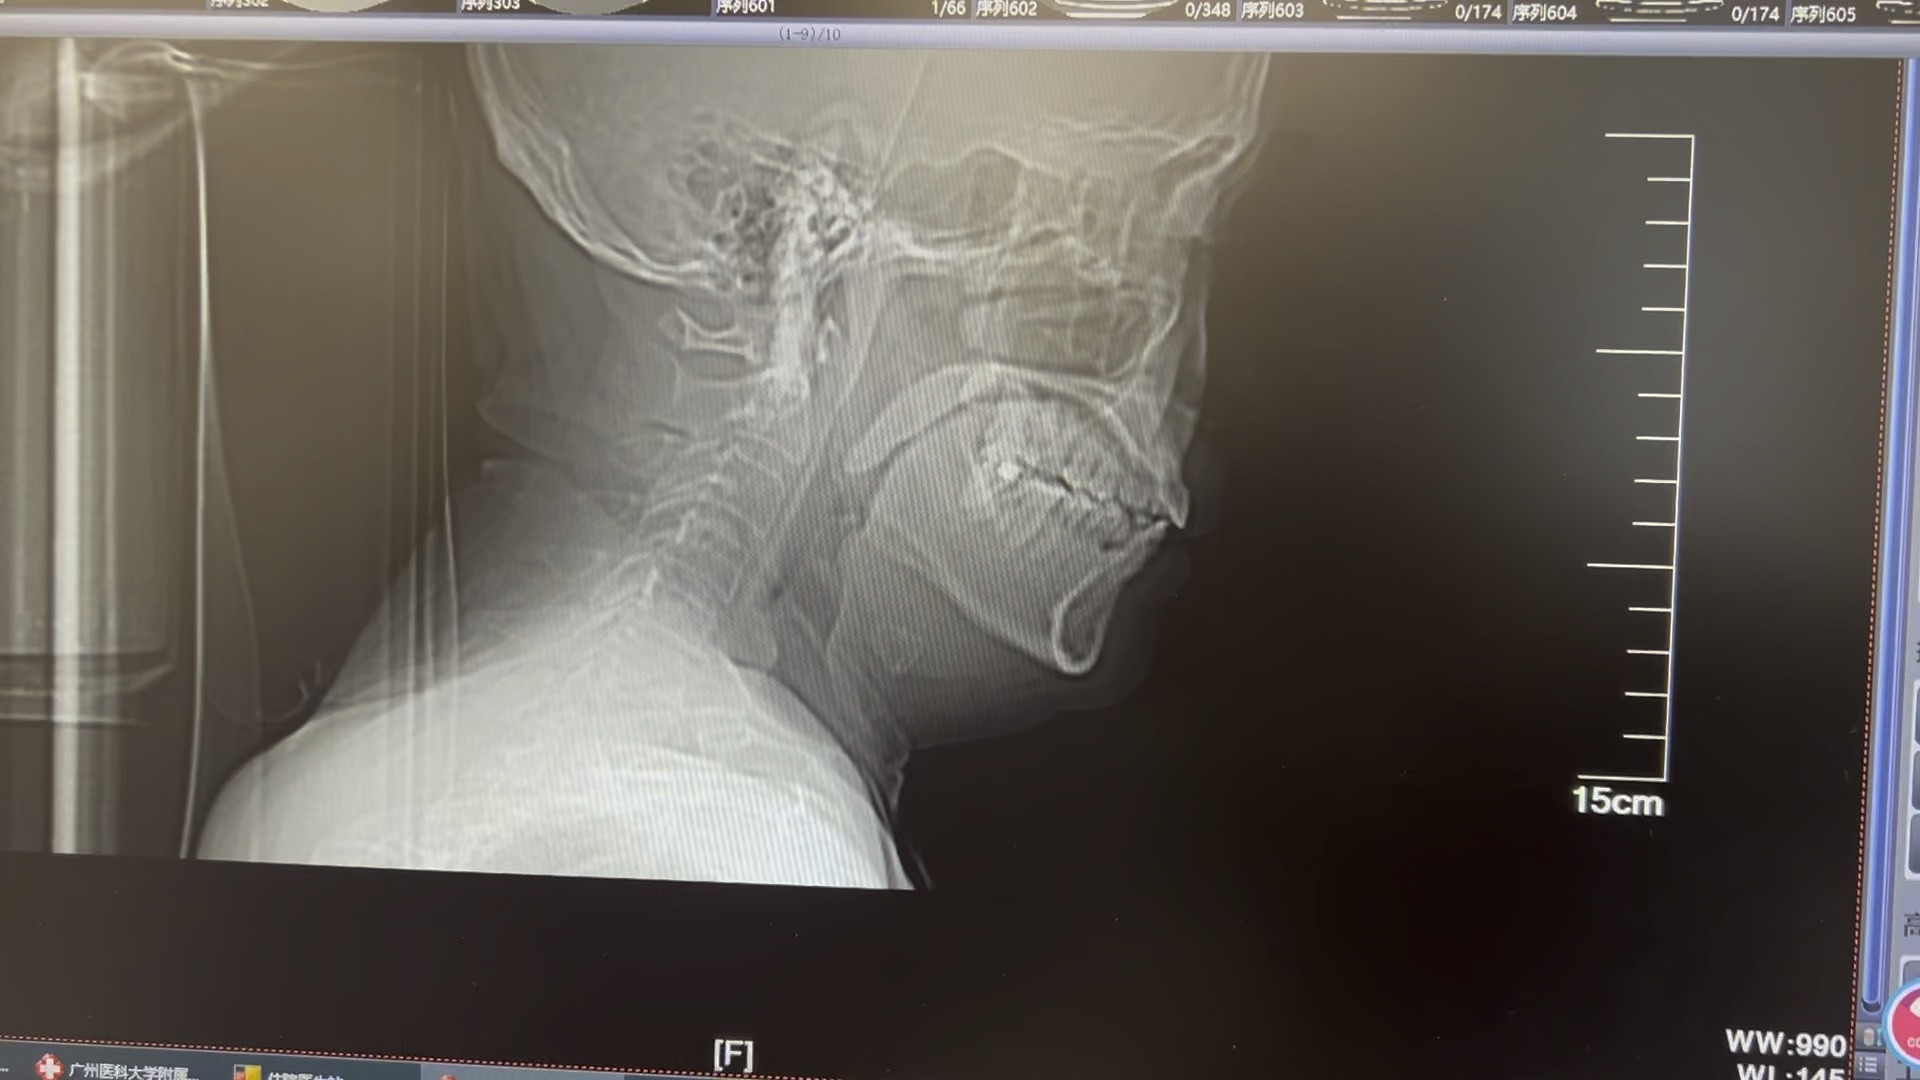

入院后查的ct,目前抗结核药依然服用